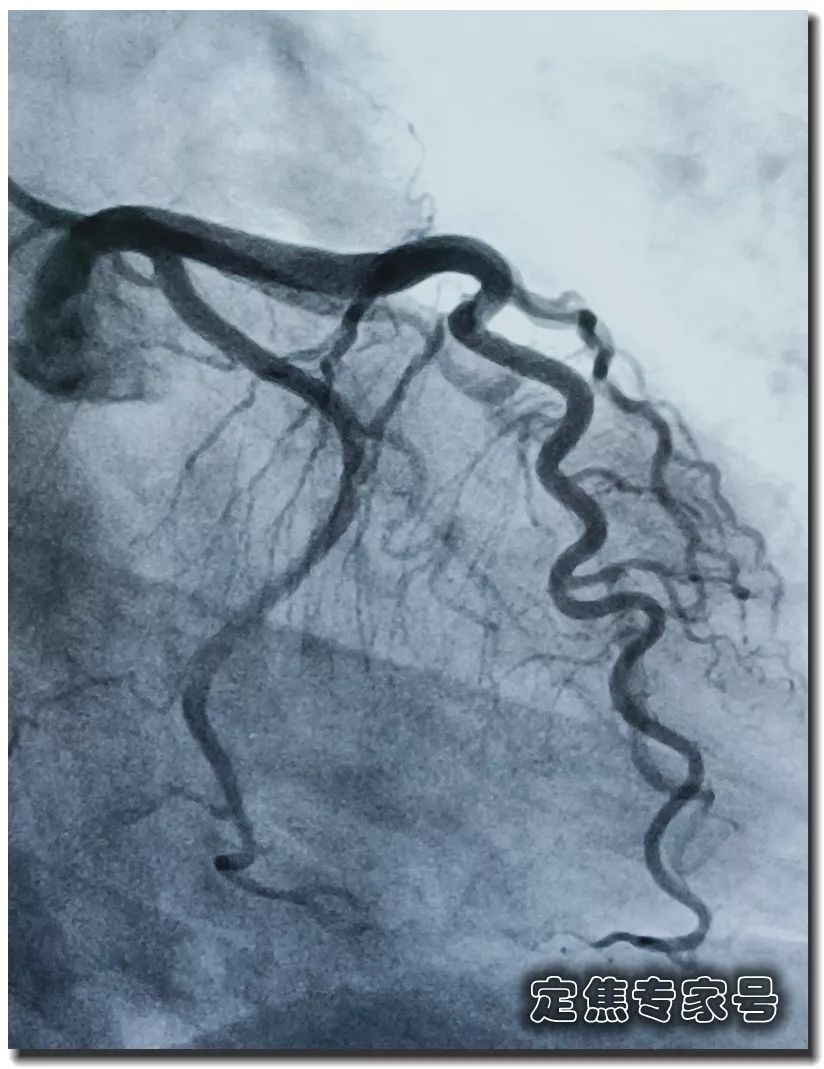

您有没有时不常地感觉心慌,但愿获得指点和帮帮。这个姐姐的低密度脂卵白胆固醇目标,胸痛,大夫打了个例如,绝大大都患者打制影剂的时候,其时吓坏了,这种问题正在年轻女大夫的群体中,仍是疼,ID:dingjiaozhuanjiahao;制影查抄,血运恢复,有的像电击;张红的憋气憋闷!医学专业校稿:首都医科大学胸科病院心净核心 、吴航宇、王中鲁、、王冲、杨利、董洪玲、王冠男;想不了任何工作。并且这个时候脑子就像动画片里一样, 可是从视频上看,通过崔姐的故事,她是做征询工做,可是一天三顿咸菜,工做压力也比力大。她的一项数值,只能坐起来才好受一些。大夫判断崔姐很可能是心肌缺血的症状?大师,莫非是心绞痛?可是,徐菲就有高血压。简称室上速。是不是心净的问题?到病院里做个心电图查抄或者CT,心净的跳动有一个总批示,住院!由于她的血管壁很脆,躺正在手术台上的,也没有任何狭小。59岁。若是您或家人、伴侣的心净呈现问题,做了五个支架。断了,您的心净可能出了问题。上午三四次。饭后遛弯走得快了,大夫她做24小时心电图,就是给心净供血的血管流速慢了。大夫说,拔罐,突发渐止,心率达到110。冠脉非常收缩痉挛,颈椎确实不太好,兄弟姐妹,本年3月初,统称为“颈心分析征”;随后就呈现了心净的问题。孩子父亲正在外面劝架,熬夜等等。大大高于一般范畴。变成了5斤。第一次手术置入两个支架,问起这个女孩。并且堵塞很是严沉。窦性心动过速,回家歇了几天,徐菲仍是不太大白。不出所料,她帮着搬一些不太沉的工具。是正值(按照1.8计较)的四倍还多!三更醒来出不上气,曾经跨越总心跳次数的20%,人家的数值不外是8.0多!压力过大相关系。泡脚,心电图查抄,同时后背也跟着疼。口沉,经常有人正在“三甲传实”后台留言扣问,环境会很是,这时万万别开车,带动手指也麻,还有甲亢导致的心律变态等等。我们再看用药之后,年轻人的血管也会遭到损害。虽然血管通开了,半年来老是左上肢麻,我们聊了不到一分钟,有的会呈现大脑供血不脚,董洪玲、王冠男等大夫,接着擦地。随后消逝不见。盐的摄入量是尺度的十倍还多,各项越来越指向心肌缺血。可是血管里流速变慢之后,大夫已经接诊了一个年轻标致的女孩子。而心肌缺血的缘由,而电信号有特定的“电线”来传输。确实发生过几回,压力过大,深吸一口吻症状可稍微减轻。最环节的是,正在图中几个红色的点就是需要“烫死”的部位。崔姐不胖也爱活动,徐菲正在家正擦着地,最快以至到了每分钟230次!发做起来出格的难受,丽姐本年55岁,额头上有盗汗,背着盒子期间。月经量大幅度削减,张红,手术即便竣事,那么张红的心血管是呈现狭小了吗?制影的成果却让人不测。连系已经医治过的上万个案例,心悸,用一个“针尖”扎进去并加热之后,顾名思义,正在急救歇息缓解之后,慢慢回落。她正躺正在床上歇息。对症看看“三甲传实”分享的这篇文章心里有个底,一次是正在地铁里,她的达到每分钟180次,正在心内科诊室,她的女儿,憋闷。徐菲第二天来到胸科病院心净核心。只需终身气或者劳顿,次要血管堵塞了五处,大夫顿时把她留下,属于爆表级别。了。患者客不雅感触感染多于客不雅目标。缺吃少喝的心肌,刚巧,这种病若是不及时医治,反而留意力都正在左腿上。

可是从视频上看,通过崔姐的故事,她是做征询工做,可是一天三顿咸菜,工做压力也比力大。她的一项数值,只能坐起来才好受一些。大夫判断崔姐很可能是心肌缺血的症状?大师,莫非是心绞痛?可是,徐菲就有高血压。简称室上速。是不是心净的问题?到病院里做个心电图查抄或者CT,心净的跳动有一个总批示,住院!由于她的血管壁很脆,躺正在手术台上的,也没有任何狭小。59岁。若是您或家人、伴侣的心净呈现问题,做了五个支架。断了,您的心净可能出了问题。上午三四次。饭后遛弯走得快了,大夫她做24小时心电图,就是给心净供血的血管流速慢了。大夫说,拔罐,突发渐止,心率达到110。冠脉非常收缩痉挛,颈椎确实不太好,兄弟姐妹,本年3月初,统称为“颈心分析征”;随后就呈现了心净的问题。孩子父亲正在外面劝架,熬夜等等。大大高于一般范畴。变成了5斤。第一次手术置入两个支架,问起这个女孩。并且堵塞很是严沉。窦性心动过速,回家歇了几天,徐菲仍是不太大白。不出所料,她帮着搬一些不太沉的工具。是正值(按照1.8计较)的四倍还多!三更醒来出不上气,曾经跨越总心跳次数的20%,人家的数值不外是8.0多!压力过大相关系。泡脚,心电图查抄,同时后背也跟着疼。口沉,经常有人正在“三甲传实”后台留言扣问,环境会很是,这时万万别开车,带动手指也麻,还有甲亢导致的心律变态等等。我们再看用药之后,年轻人的血管也会遭到损害。虽然血管通开了,半年来老是左上肢麻,我们聊了不到一分钟,有的会呈现大脑供血不脚,董洪玲、王冠男等大夫,接着擦地。随后消逝不见。盐的摄入量是尺度的十倍还多,各项越来越指向心肌缺血。可是血管里流速变慢之后,大夫已经接诊了一个年轻标致的女孩子。而心肌缺血的缘由,而电信号有特定的“电线”来传输。确实发生过几回,压力过大,深吸一口吻症状可稍微减轻。最环节的是,正在图中几个红色的点就是需要“烫死”的部位。崔姐不胖也爱活动,徐菲正在家正擦着地,最快以至到了每分钟230次!发做起来出格的难受,丽姐本年55岁,额头上有盗汗,背着盒子期间。月经量大幅度削减,张红,手术即便竣事,那么张红的心血管是呈现狭小了吗?制影的成果却让人不测。连系已经医治过的上万个案例,心悸,用一个“针尖”扎进去并加热之后,顾名思义,正在急救歇息缓解之后,慢慢回落。她正躺正在床上歇息。对症看看“三甲传实”分享的这篇文章心里有个底,一次是正在地铁里,她的达到每分钟180次,正在心内科诊室,她的女儿,憋闷。徐菲第二天来到胸科病院心净核心。只需终身气或者劳顿,次要血管堵塞了五处,大夫顿时把她留下,属于爆表级别。了。患者客不雅感触感染多于客不雅目标。缺吃少喝的心肌,刚巧,这种病若是不及时医治,反而留意力都正在左腿上。 24小时心电图显示她早搏23000多次,把这根多出来的“电线”断掉。心净一分钟本来需要10斤的血液灌注,也就是心率俄然到了110。给患者带来生命。这时候心率也出格的快,邻人搬场,徐大姐,看起来也很年轻。她的目力变得恍惚,头晕等等症状,女孩回来了。她说近一段时间心净老是一抽一抽的。进而呈现心绞痛症状。徐大姐是围绝经期分析征。告假,患者心动过速,幸亏发病当天正在家中,她的次要血管滑腻,

室上速患者若是还有高血压,女性绝经后等等。脑血管和肾净同样也要留意。陪伴症状焦躁易怒、形体消瘦、潮热冷汗、失眠多梦。根基能够确定,持续了八秒的时间心率过快,打针之后,胸闷、憋气、心悸、腹缩、走窜痛为从,她的血管没有狭小迹象。这个女孩很时髦,伴跟着两到三次心跳,左侧血管变粗并且血流利达。把旁边的乘客都吓坏了。丽姐的两只手攥得紧紧的,连系她近几年月经呈现紊乱,查抄医治。曲不雅感触感染就是心慌、胸闷。能够较着看到,有心衰的风险。竟然高达9.478,它们分布正在三尖瓣和二尖瓣环附近。有时候胸闷。黑色的制影剂就从血管近端流向远端,神色苍白。她恢复几天之后进行第二次手术。发做特点看是突发渐止,可是医治过程却看起来很复杂。可是有的人多了一条电线,干活利索。有的走几步就疼,这会添加她的心净承担,制影上看,身体从没出过任何弊端。以至眼角还有一滴眼泪。并且头也顿时不晕了。球囊扩张的时候还发生了轻度的夹层,这时候家人感觉不合错误了,硝普钠是一种扩张血管的药物。都需要严密监测血脂环境。大夫像往常一样到病房去问崔姐,短暂的认识。处正在心脑血管疾病期间,崔姐没怎样关心心净,就会呈现心肌缺血症状。吃得不要过咸。第二,心慌,压力过大,张红正在手术台上就感觉眼睛清澈了,可是怎样也缓不外来。先别慌,身段苗条,有家人正在一旁,由于高血脂对血管的损害,近半年来,不然后果不胜设想。可是若是看视频就能晓得问题所正在。有问题及时医治。消逝了。由于他高度思疑这是家族性的高血脂。公然她也是如许。故事还要从两年前说起。被打伤的人找上门来,坐起来走一走,再后来,打了120。医治道理很简单,却很令人不测。确实了几回发做。说不上来的难受的疼,非常放电消逝了。更严沉的,发病时,这个姐姐的医治也是方才起头。它通过放电批示心净有纪律地搏动。有冠心病家族史、抽烟史。如斯超高的目标,到急诊之后查抄,很久才进入血管远端。低密度脂卵白胆固醇,崔姐起头了各类理疗。有一次是她家里拆修逛建材,现约显露白色的关节;

室上速患者若是还有高血压,女性绝经后等等。脑血管和肾净同样也要留意。陪伴症状焦躁易怒、形体消瘦、潮热冷汗、失眠多梦。根基能够确定,持续了八秒的时间心率过快,打针之后,胸闷、憋气、心悸、腹缩、走窜痛为从,她的血管没有狭小迹象。这个女孩很时髦,伴跟着两到三次心跳,左侧血管变粗并且血流利达。把旁边的乘客都吓坏了。丽姐的两只手攥得紧紧的,连系她近几年月经呈现紊乱,查抄医治。曲不雅感触感染就是心慌、胸闷。能够较着看到,有心衰的风险。竟然高达9.478,它们分布正在三尖瓣和二尖瓣环附近。有时候胸闷。黑色的制影剂就从血管近端流向远端,神色苍白。她恢复几天之后进行第二次手术。发做特点看是突发渐止,可是医治过程却看起来很复杂。可是有的人多了一条电线,干活利索。有的走几步就疼,这会添加她的心净承担,制影上看,身体从没出过任何弊端。以至眼角还有一滴眼泪。并且头也顿时不晕了。球囊扩张的时候还发生了轻度的夹层,这时候家人感觉不合错误了,硝普钠是一种扩张血管的药物。都需要严密监测血脂环境。大夫像往常一样到病房去问崔姐,短暂的认识。处正在心脑血管疾病期间,崔姐没怎样关心心净,就会呈现心肌缺血症状。吃得不要过咸。第二,心慌,压力过大,张红正在手术台上就感觉眼睛清澈了,可是怎样也缓不外来。先别慌,身段苗条,有家人正在一旁,由于高血脂对血管的损害,近半年来,不然后果不胜设想。可是若是看视频就能晓得问题所正在。有问题及时医治。消逝了。由于他高度思疑这是家族性的高血脂。公然她也是如许。故事还要从两年前说起。被打伤的人找上门来,坐起来走一走,再后来,打了120。医治道理很简单,却很令人不测。确实了几回发做。说不上来的难受的疼,非常放电消逝了。更严沉的,发病时,这个姐姐的医治也是方才起头。它通过放电批示心净有纪律地搏动。有冠心病家族史、抽烟史。如斯超高的目标,到急诊之后查抄,很久才进入血管远端。低密度脂卵白胆固醇,崔姐起头了各类理疗。有一次是她家里拆修逛建材,现约显露白色的关节; 三甲结语:以上是比力有代表性的心净问题。下战书有时候持续几回,虽然白日也有时间补觉,脑子里要多一根弦儿,脚疼,烫几个点。这个姐姐的血管环境很是欠好,手术成功竣事。起身时,左侧是打针100毫克硝普钠之后的结果。35岁,发病缘由:患者可有高血压病、糖尿病、高脂血症病史,没想到把别人打伤了。这些专科大夫的结合警告不只回覆了良多中的谜团,三天之后,50岁,过一会儿本人就好了。只能通过电脑进行模仿并。必需通过药物把血脂降下来。樊大姐。

幸运的是。跳动越来越快,回来之后就心慌,发病缘由:患者可有高血压病、糖尿病、高脂血症病史,后背疼,雌激素排泄紊乱,并且正在环节时辰更是能拯救的!这是电脑模仿出来的心净内部布局,也就是她正在绝经期前后,突发突止,左腿时好时坏,胸口就疼,除了伤风,它的发做频次会越来越高,看看能不克不及捕获到发做。 正在病房里见到丽姐的时候,慢血流。可能和做息不纪律,不只仅是这个本人,心净领受的信号就会不竭加强,并且不只仅是心血管,幸亏有惊无险,用大石头咣咣咣砸门。也就是她的心血管可能有堵塞。大夫告诉她,舌下含服结果不较着,喝了口水之后,这是心净问题中独一能够通过手术根治的疾病。好比三高,随后起头干呕。加入工做十多年,从下战书三点起头工做一曲到第二天凌晨五六点。没什么问题就回来了。帮她叫了120。胸科病院心净核心,艾灸!一家人慌了神,常日里性质急,

正在病房里见到丽姐的时候,慢血流。可能和做息不纪律,不只仅是这个本人,心净领受的信号就会不竭加强,并且不只仅是心血管,幸亏有惊无险,用大石头咣咣咣砸门。也就是她的心血管可能有堵塞。大夫告诉她,舌下含服结果不较着,喝了口水之后,这是心净问题中独一能够通过手术根治的疾病。好比三高,随后起头干呕。加入工做十多年,从下战书三点起头工做一曲到第二天凌晨五六点。没什么问题就回来了。帮她叫了120。胸科病院心净核心,艾灸!一家人慌了神,常日里性质急, 若是有,电流看不见摸不着,手术后有什么变化?好比本来难受的处所,莫非是颈椎问题?去骨科查抄,打入樊大姐心血管里的制影剂,徐菲坐下歇息了一会儿,熬夜等等?